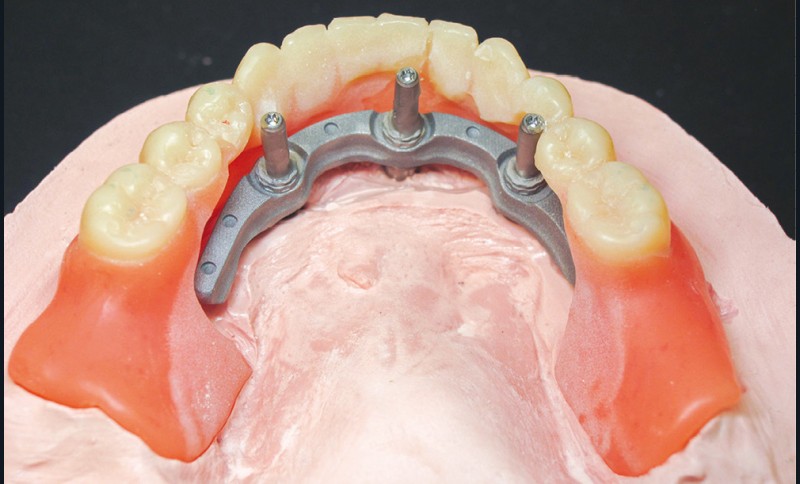

Après démontage et nettoyage du dispositif implantoporté, la barre Trefoil est vissée passivement [7] sur ses analogues grâce à un mécanisme judicieux de rotules compensatrices. Un dernier contrôle de coaptation barre/prothèse est réalisé (fig. 6). L’ensemble est sablé et solidarisé par une résine chémopolymérisable. Après polymérisation, suppression des extensions, aménagement des accès prophylactiques et maquillage composite par addition acté, le bridge d’usage est mis en charge immédiatement (fig. 7).